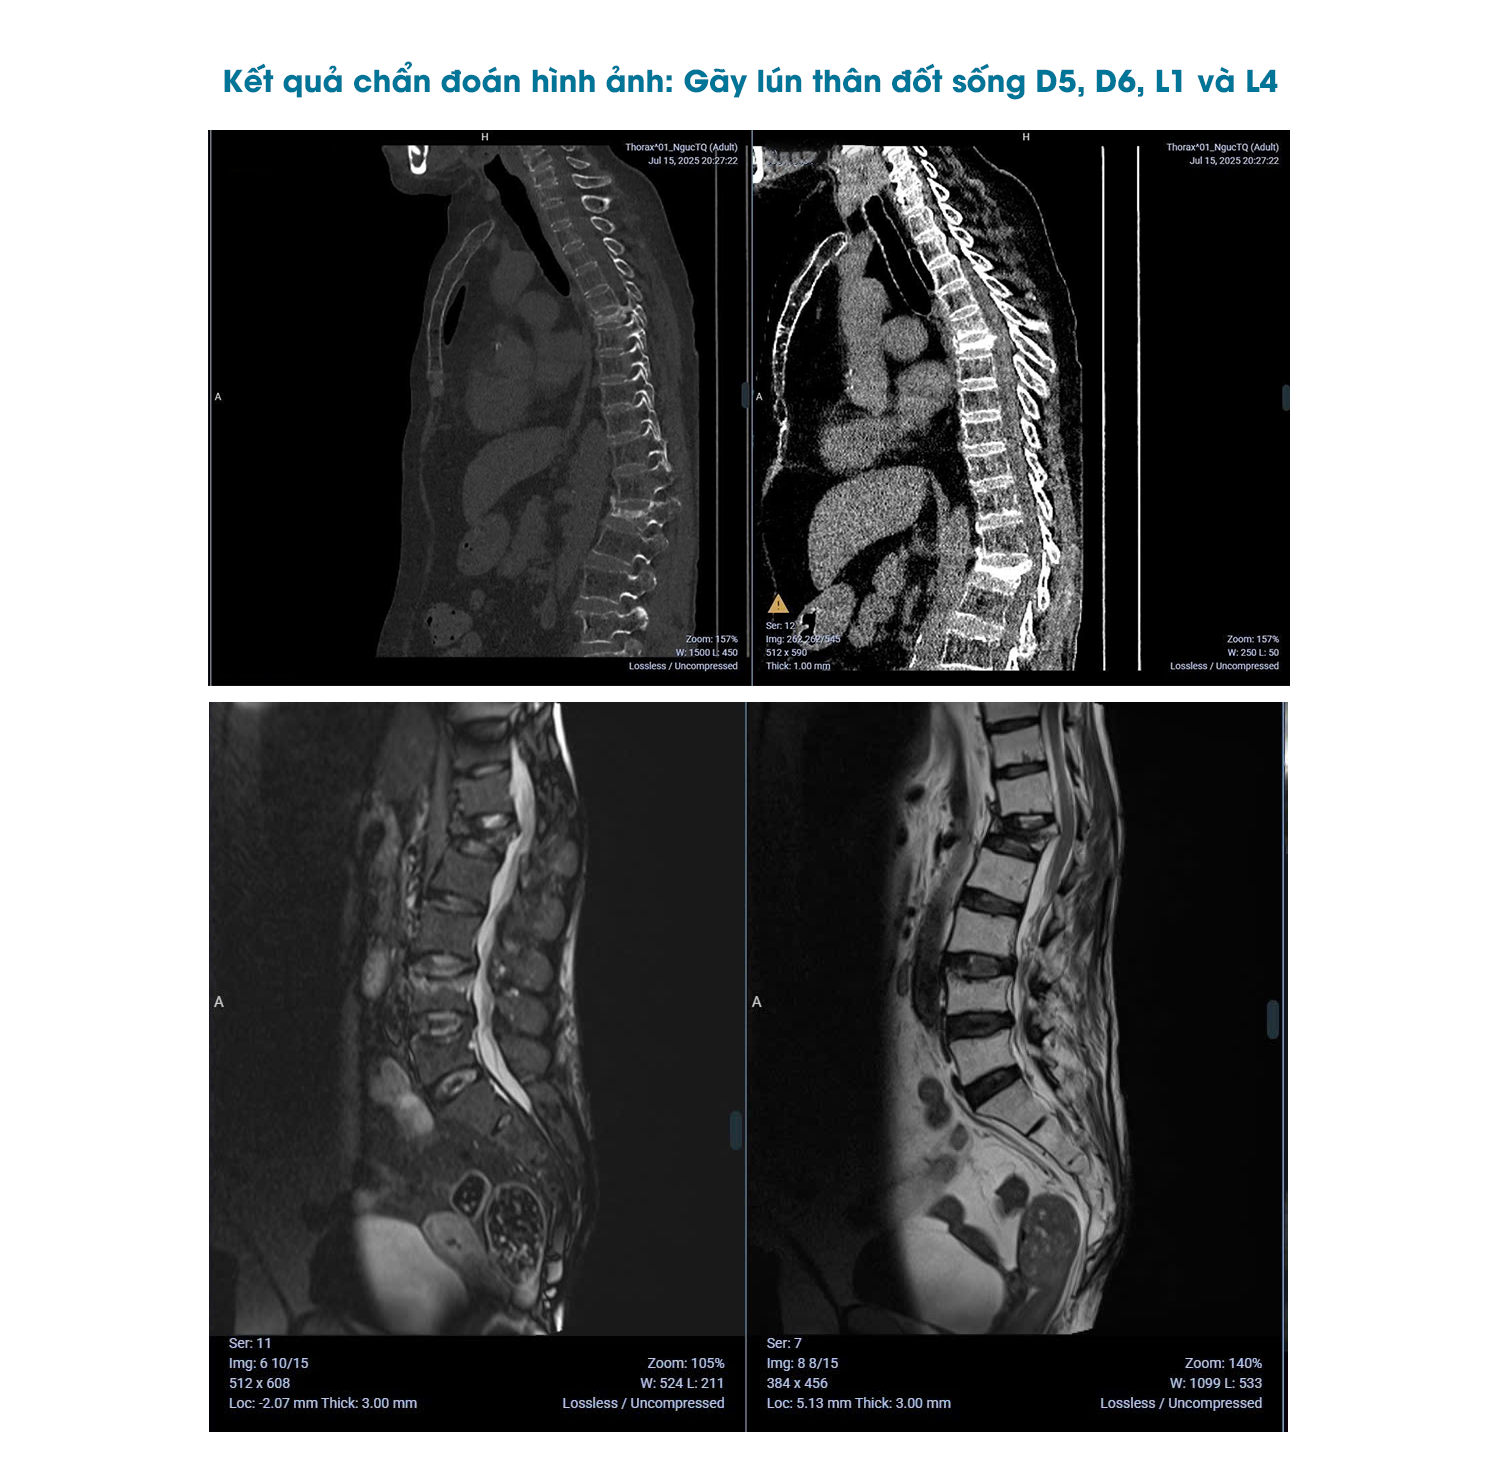

Phẫu thuật “thần tốc” trong 30 phút

Tại AIH, sau khi thăm khám lâm sàng và dựa trên kết quả chẩn đoán hình ảnh, Bác sĩ CKI Nguyễn Mạnh Hùng chẩn đoán bệnh nhân gãy cột sống nhiều tầng, gãy lún thân đốt sống D5, D6, L1 và L4, chèn ép tủy - chùm đuôi ngựa, đây là tình trạng cấp cứu ngoại thần kinh nghiêm trọng, có nguy cơ gây liệt vĩnh viễn nếu không can thiệp kịp thời. Trước đó, những tổn thương này đã không được chẩn đoán và xử trí đúng hướng, khiến cơn đau ngày càng tăng, vận động hạn chế và nguy cơ tổn thương thần kinh tiến triển nhanh.